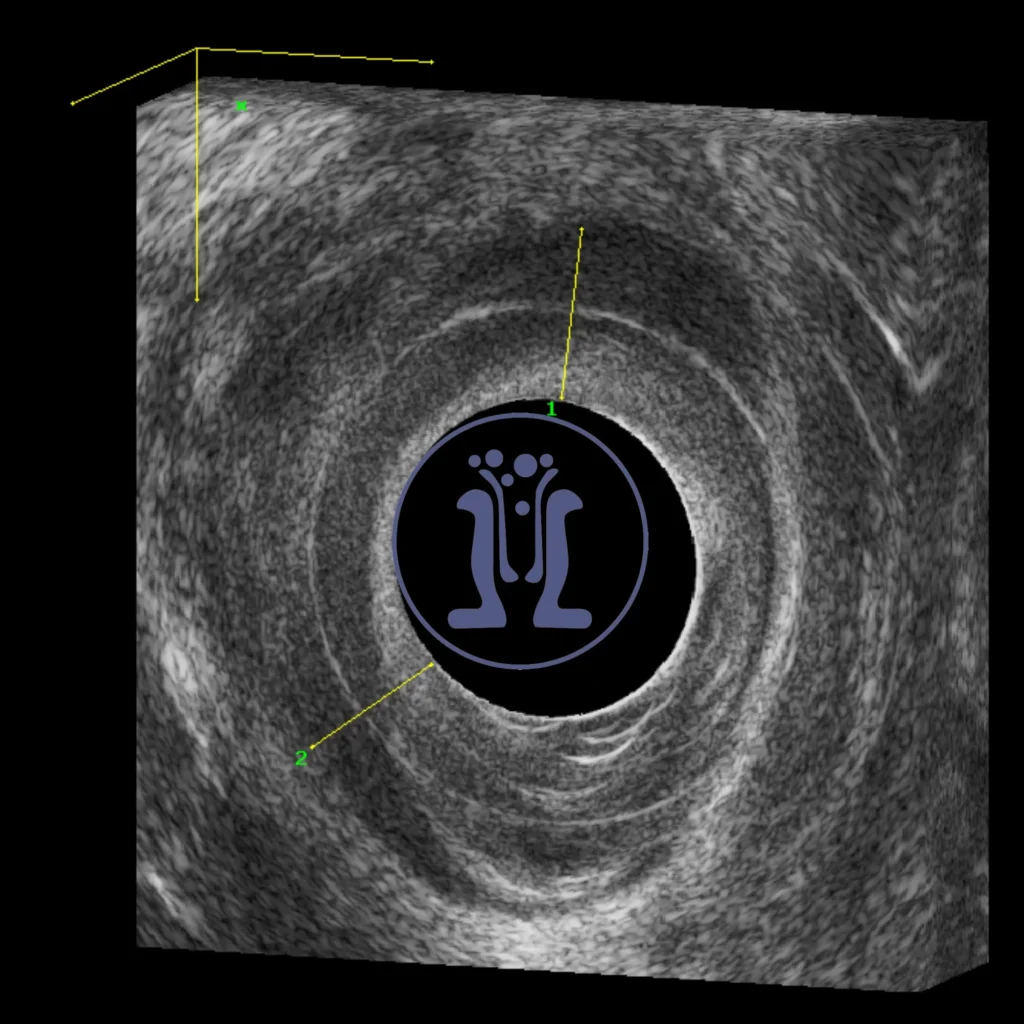

Το ενδοπρωκτικό υπερηχογράφημα δείχνει μία κύστη στο οπίσθιο άνω τεταρτημόριο του πρωκτικού σωλήνα με χαρακτήρες οπισθοορθικής κύστης. Η οπίσθοορθική κύστη είναι μία κύστη που αναπτύσσεται πίσω από το ορθού και πιθανότατα προκαλείται από παραμονή και περαιτέρω ανάπτυξη εμβρυικού υπολείμματος.